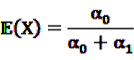

and  be random variables to describe the occurrence of drug exposure i and ADR j, respectively. The a priori expectations of X and Y are obtained as:

be random variables to describe the occurrence of drug exposure i and ADR j, respectively. The a priori expectations of X and Y are obtained as: and